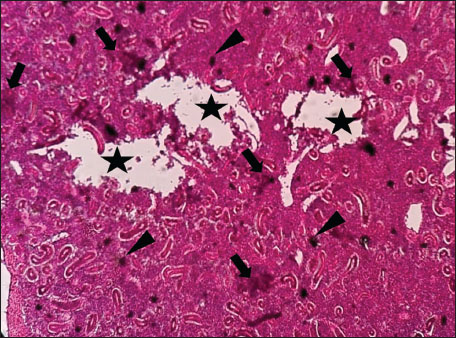

Histopathological examination of the kidney tissues of L. sceleratus revealed multiple alterations. Prominent melanomacrophage centers (MMCs), necrotic areas, dilatation of Bowman’s capsules, and vacuolar degeneration were observed (Fig. 1), associated with interstitial lymphohematopoietic tissue (Fig. 2). Dilated and congested blood vessels and extensive MMCs were also noted (Fig. 3). Renal degeneration surrounding lymphohematopoietic tissue, large clusters of MMCs, and thickened, congested vessel walls within fibrotic areas were evident (Fig. 4). Atrophic renal degeneration with necrotic and vacuolar changes was observed (Fig. 5). Severe inflammatory infiltration of lymphatic cells and granulomas with necrotic centers, surrounded by fibrous tissue, was detected (Figs. 67).

Fig. 4. Histopathology of the kidney in an adult L. sceleratus showing renal degeneration surrounding lymphohematopoietic tissue (stars), large MMC clusters (head arrows), and congested, dilated, thickened vessel walls within fibrotic areas (thin arrows). ×400 H&E.

The present study revealed pronounced histopathological alterations in both the kidneys and gills of L. sceleratus collected along the Libyan coast. Kidney lesions, including tubular degeneration, Bowman’s capsule dilatation, proliferation of MMCs, vascular congestion, and inflammatory infiltration, were associated with histologically detected structures, but no parasitic structures were detected in kidney tissues. These patterns are commonly reported in marine teleosts exposed to chronic environmental stressors (Ali et al., 2014; Steinel and Bolnick, 2017; Carreras-Colom et al., 2022). These lesions should be interpreted as descriptive indicators of physiological stress rather than direct evidence of chemical pollution or causality, consistent with Flores-Lopes and Thomaz (2011). Vascular abnormalities, including congestion and thickened vessel walls, were evident, which may reflect chronic circulatory disturbances or inflammatory responses rather than acute toxicity (Bernet et al., 1999; Thophon et al., 2003). Interstitial lymphohematopoietic tissue, inflammatory cell infiltration, and granulomatous formations suggest that parasitic or microbial challenges could contribute to renal lesions. Despite these histopathological changes, the sampled fish appeared healthy at capture, demonstrating the potential physiological resilience of marine teleosts. Fish kidneys possess compensatory mechanisms, and gills serve critical osmoregulatory and excretory functions, allowing survival despite structural alterations (Evans et al., 2005; Hwang et al., 2011; Hinton et al., 2018; Leone et al., 2018). Gradual development of renal lesions likely enables adaptation without acute organ failure.